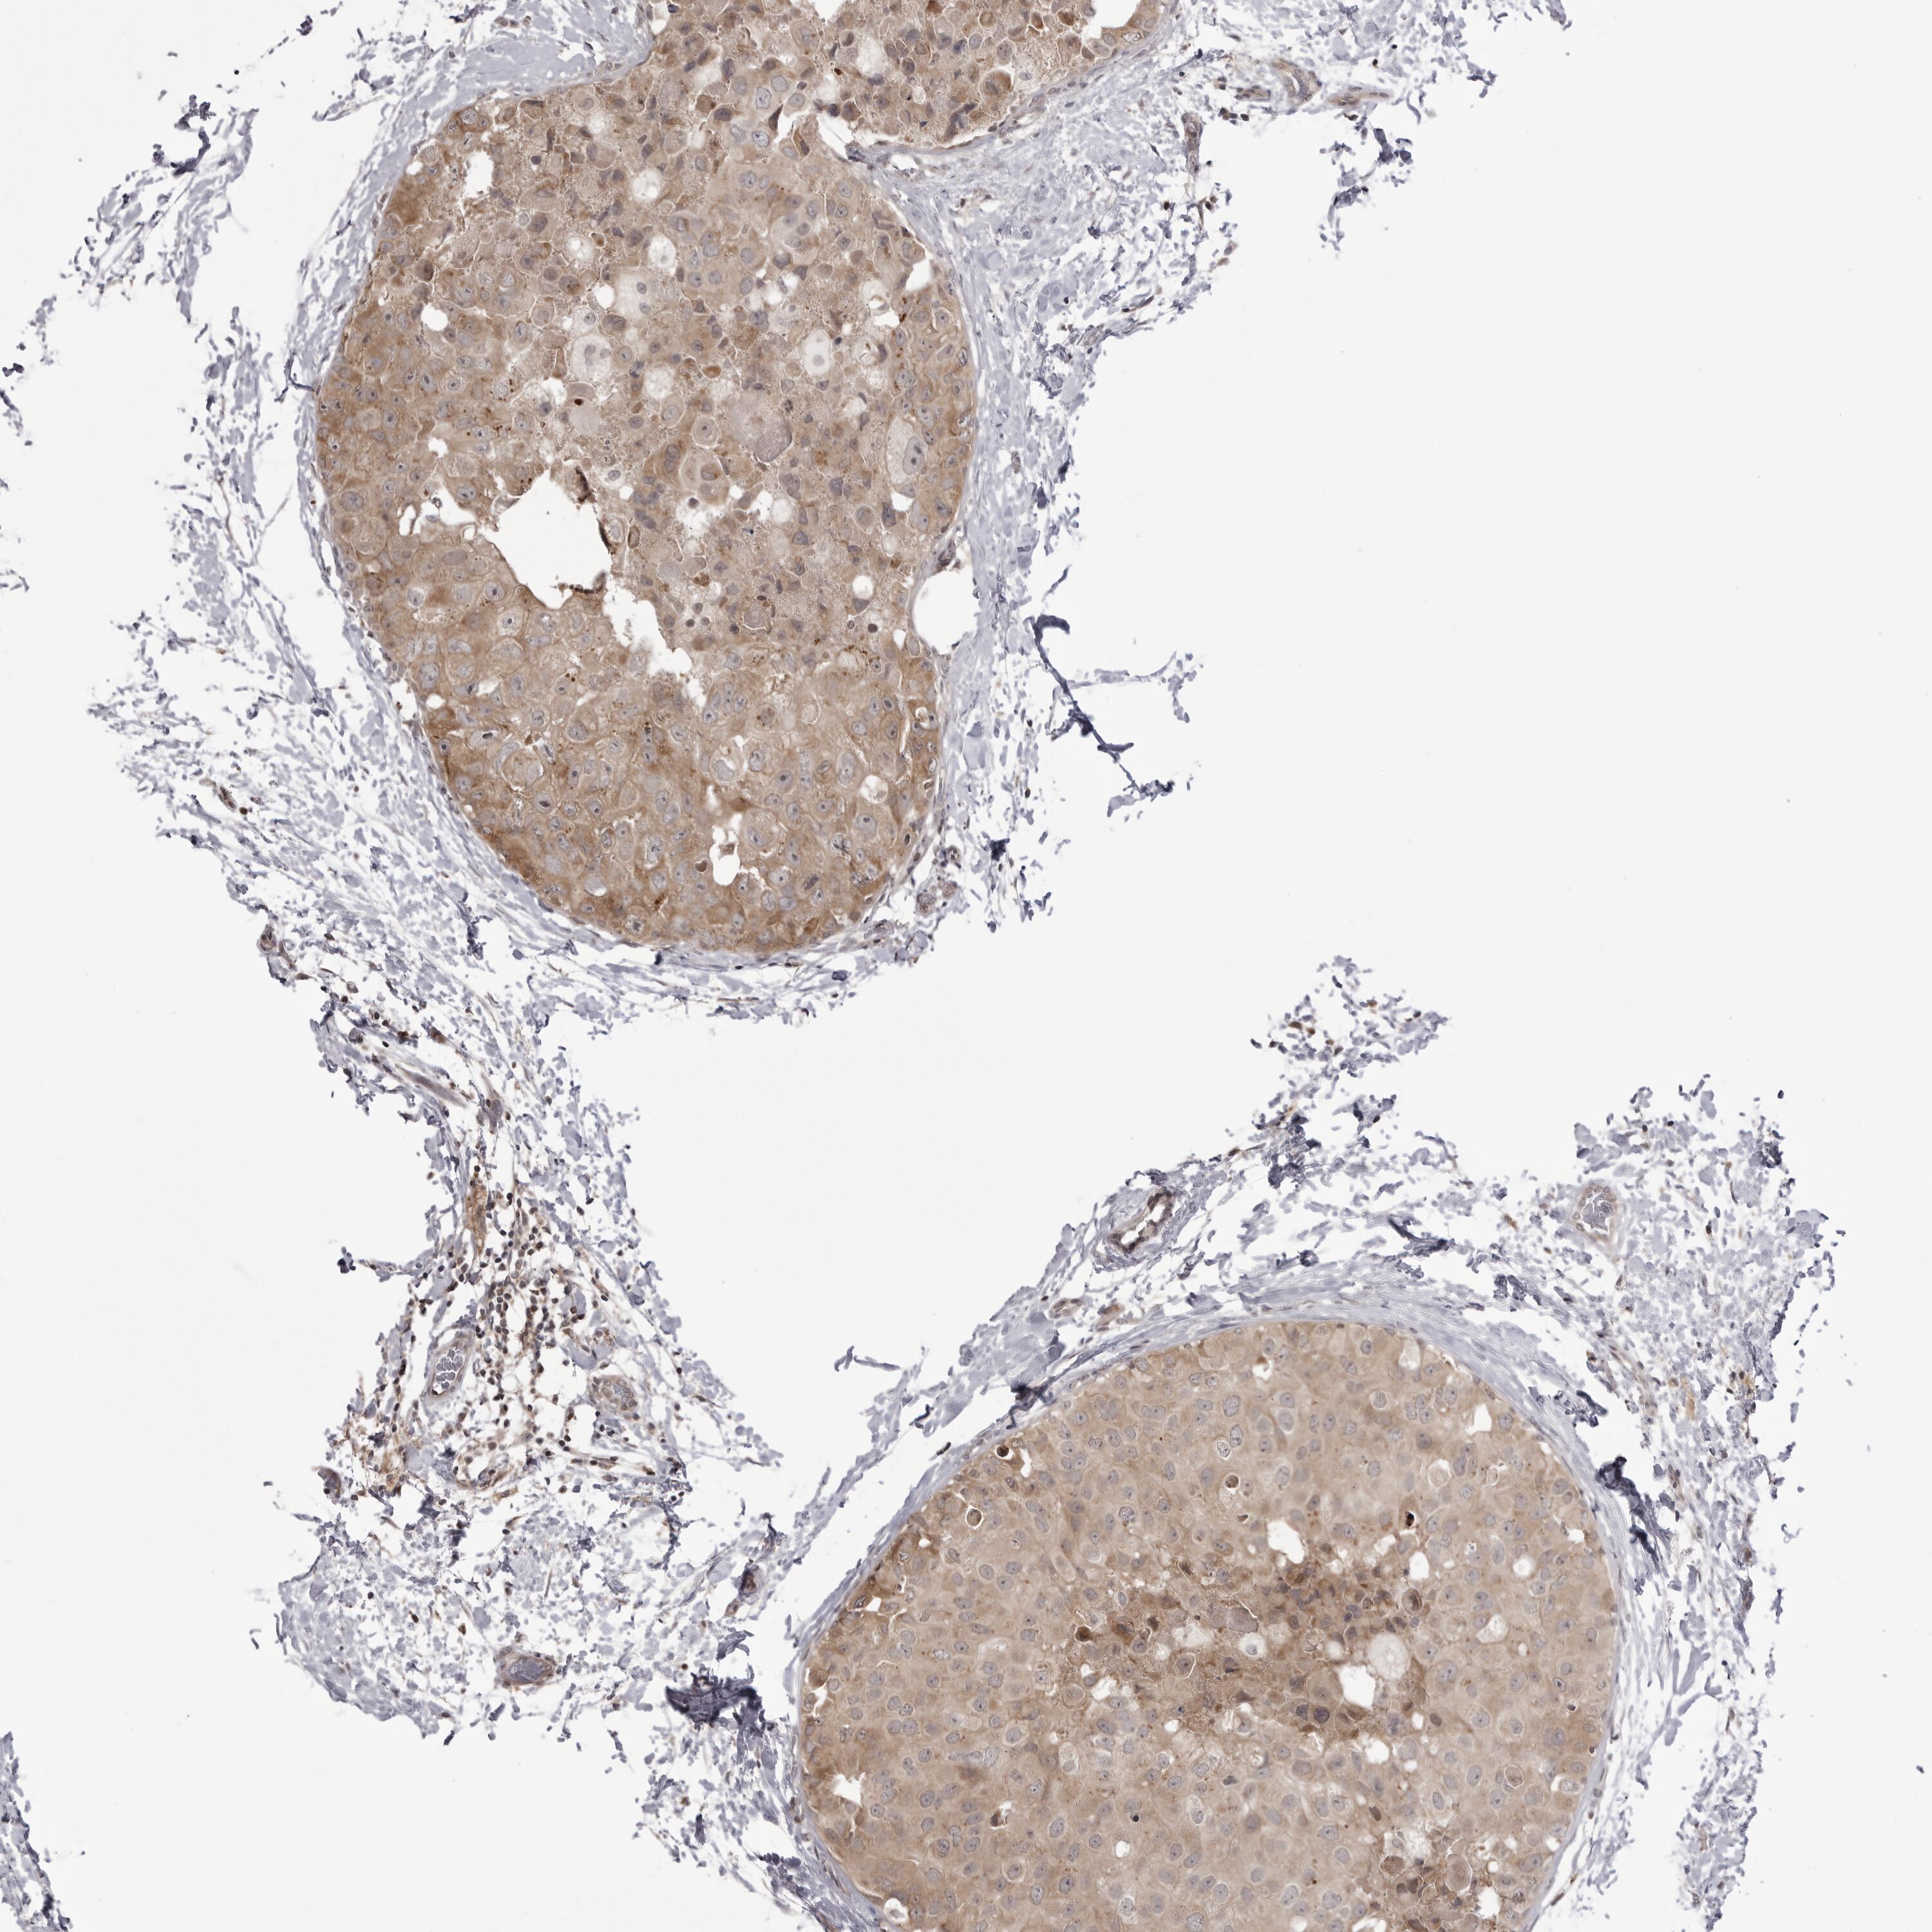

CANCER BREAST CANCER Show tissue menu

BRCA TCGA BRCA VALIDATION PROTEIN EXPRESSION